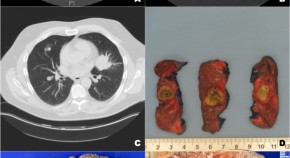

The editors of Modern Pathology present a collection of recent papers that focus on pulmonary pathology. The topics include COVID-19, non-small cell lung cancer, mesothelioma, idiopathic pulmonary fibrosis and much more. These articles are not the basis for the upcoming Pulmonary Pathology Long Course; rather, they are additional material that may be of interest to the attendees. For more information on the 2021 virtual Long Course at the USCAP 110th Annual Meeting, please visit Long Course - Pulmonary Pathology: Practical Problems and Solutions.